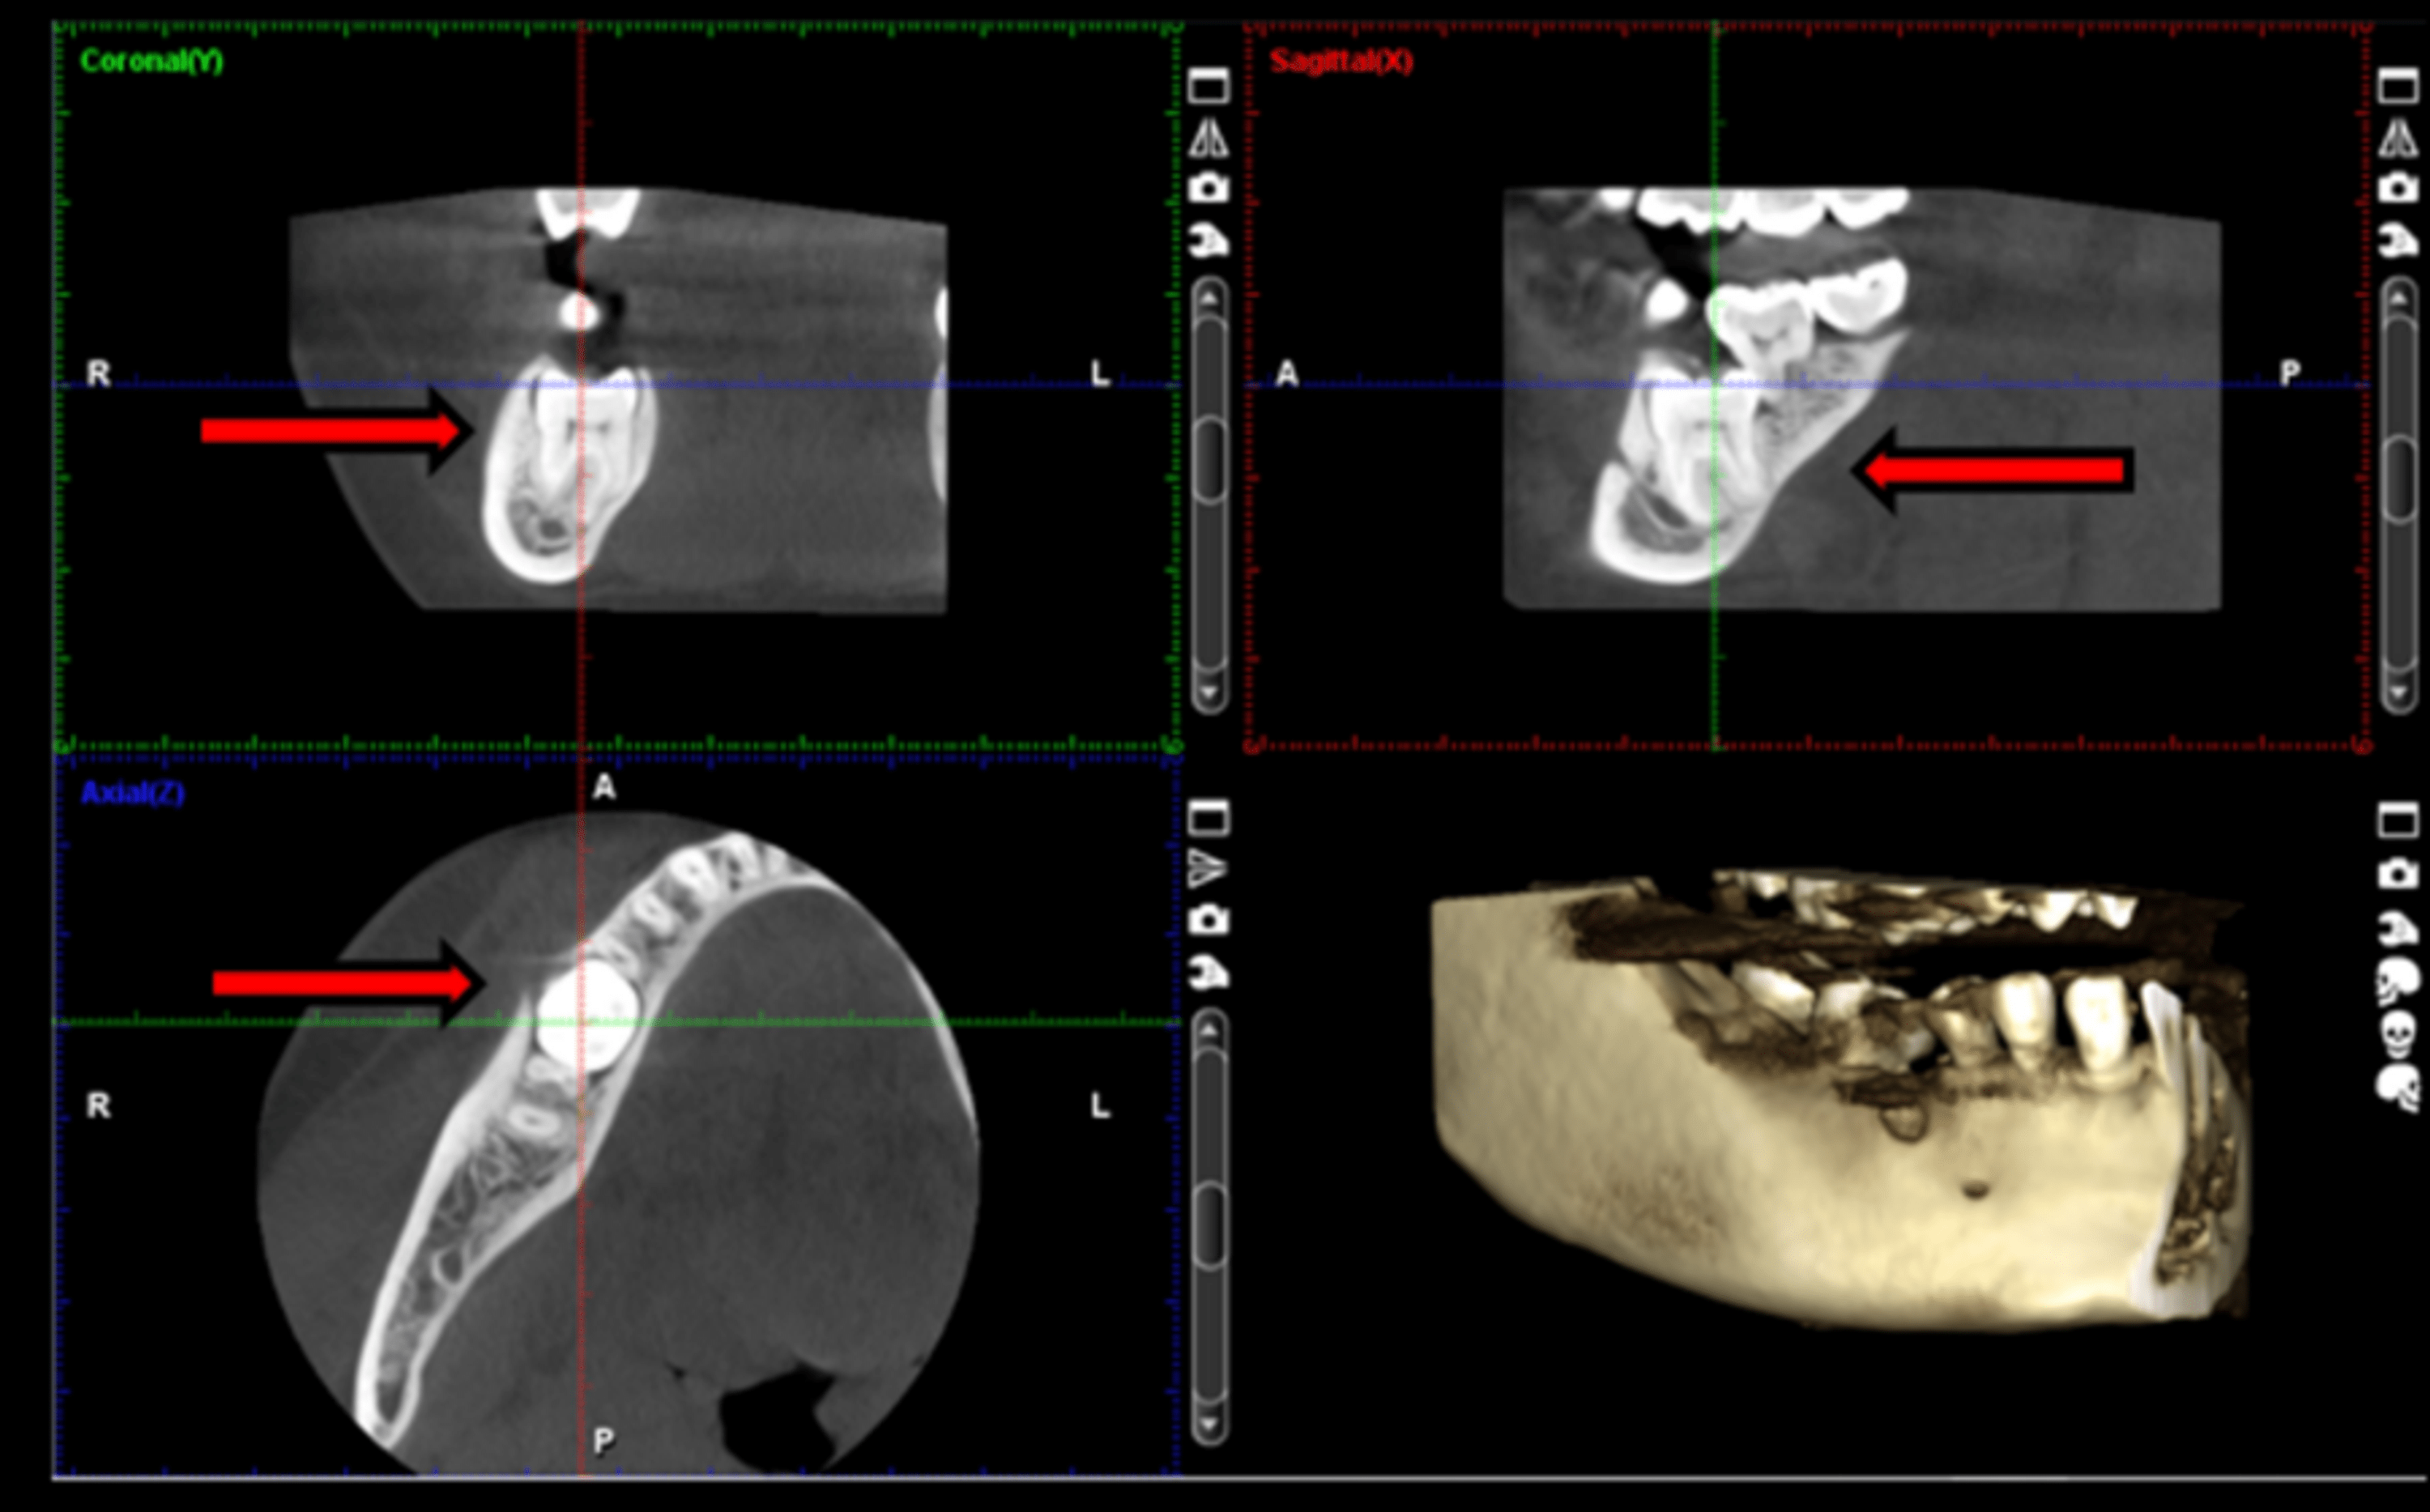

From www.jsmcentral.org

A DeeplyImpacted Mandibular Third Molar with its Root Protruding from What Is Impacted Molar This may be due to a. A tooth is referred to as ‘ impacted ’ when it fails to fully erupt and remains fully or partially inside the gums. If you have an impacted tooth and it's causing you discomfort, or your doctor suspects it may lead to dental complications, surgery may be required. Impacted wisdom teeth happen when your. What Is Impacted Molar.